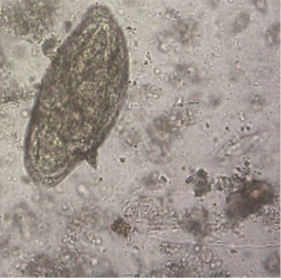

What is the specimen on stool microscopy?

Schistosoma mansoni

Schistosoma mansoni egg measuring ~150 long by 55 μm wide.

Light yellow/brown, elongated oval shape and with a characteristic prominent lateral spine near the posterior end.

Contains a miracidium.